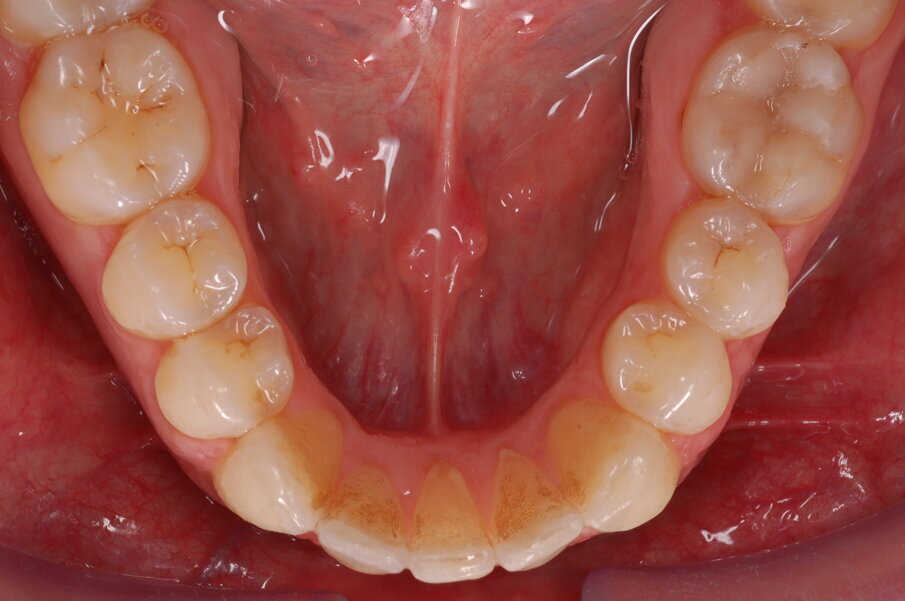

Diagnosi ed eziologia Un uomo sano di 39 anni si è presentato nel nostro studio ortodontico lamentando un aspetto dentale poco attraente e la paura della chirurgia ortognatica proposta da un altro ortodontista. Clinicamente, il profilo del paziente era rettilineo e la vista frontale non mostrava alcuna asimmetria facciale. L’esame funzionale non ha rivelato alcuna deviazione mandibolare o riduzione dei movimenti. Il paziente non aveva dolori articolari e non sono stati rilevati rumori articolari. Era presente una lieve occlusione molare bilaterale di Classe II, un morso aperto e un grave affollamento in entrambe le arcate. L’affollamento era particolarmente grave nell’arcata mandibolare, sebbene mancasse l’incisivo centrale mandibolare destro. Gli incisivi mascellari erano di piccole dimensioni, suggerendo una discrepanza dell’indice di Bolton se fossero stati presenti tutti e quattro gli incisivi mandibolari. Erano inoltre presenti un morso incrociato nella regione dell’incisivo laterale superiore sinistro e una grave rotazione distale del secondo premolare mandibolare sinistro (Figg. 1-8).

Figg. 1-8_Fotografie facciali e intraorali pre-trattamento.